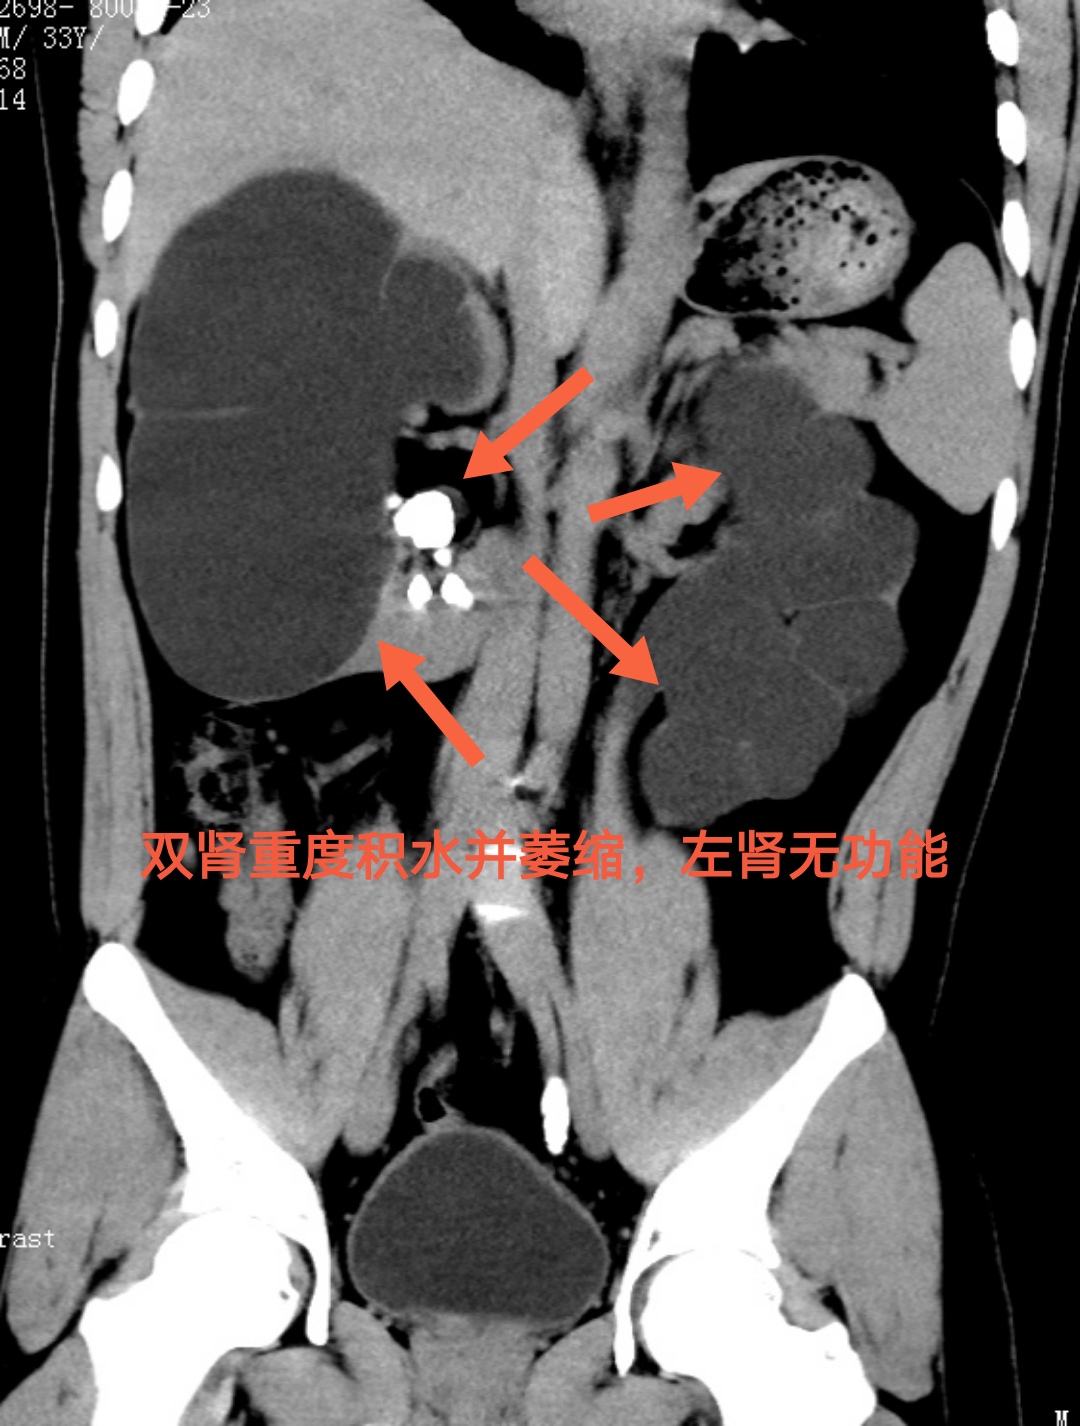

湖南益阳30岁的小申刚入职公司不久,平素身强体健,从未有过肾周不适及腰痛。这次,却在公司常规体检时发现双肾重度积水,这才赶紧到湖南省人民医院泌尿四科就诊。

接诊的泌尿四科主任杨科详细询问病情,经进一步CT检查发现,小申的双侧肾输尿管里长了结石,严重肾积水是因为结石长期坎顿梗阻所导致的。由于没有任何症状,正值壮年的他也从未体检,并不知道结石在体内已对身体造成了伤害,长期下来,左肾已经完全丧失了功能。最终,小申在泌尿四科成功接受手术治疗,遗憾的是,他失去了一个肾。